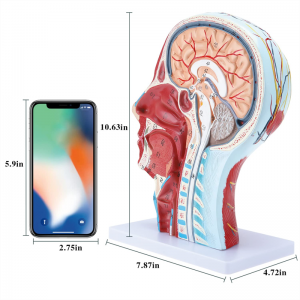

| ਉਤਪਾਦ ਦਾ ਨਾਮ | ਮਾਸਪੇਸ਼ੀ ਨਿ ur ਰੋਵਸਕੁਲਰ ਮਾਡਲ ਦੇ ਨਾਲ ਮਨੁੱਖੀ ਖੋਪੜੀ |

| ਸਮੱਗਰੀ | ਪੀਵੀਸੀ |

| ਮਾਪ | 21 * 12 * 27 ਸੈਮੀ |

| ਫੀਚਰ | ਮਾਡਲ ਸਿਰ ਅਤੇ ਗਰਦਨ ਦੇ ਅੰਦਰੂਨੀ ਅਤੇ ਬਾਹਰੀ ਪਾਸਿਆਂ ਦੇ ਅੰਦਰੂਨੀ ਰੂਪਨ ਵਿਗਿਆਨ ਦੇ ਨਾਲ-ਨਾਲ ਖੂਨ ਦੀਆਂ ਨਾੜੀਆਂ ਅਤੇ ਨਾੜਾਂ ਦੇ structures ਾਂਚਿਆਂ ਦਾ ਸਥਾਨਕ ਰੂਪ ਵਿਗਿਆਨ ਦਰਸਾਉਂਦਾ ਹੈ, ਅਤੇ ਇੱਥੇ 84 ਹਿੱਸੇ ਹਨ ਜੋ ਕੁੱਲ ਵਿੱਚ ਸੰਕੇਤ ਦਰਸਾਉਂਦੇ ਹਨ. |

【1: 1 ਦਾ 1 ਜੀਵਨ ਬਚਾਉਣ ਵਾਲਾ ਹਿੱਸਾ 1: 1 ਕੁਦਰਤੀ ਵੱਡੇ ਸਿਰ ਅਤੇ ਗਰਦਨ ਸਤਹੀ ਸੰਚਾਲਕ ਨਾਚਲਣ ਮਾਸਪੇਸ਼ੀ ਮਾਡਲ (ਸੱਜੇ ਪਾਸੇ). ਵਧੀਆ ਕਾਰੀਗਰ. ਐਨਾਟੋਮਿਕਲ ਵਿਸ਼ੇਸ਼ਤਾਵਾਂ ਦੀ ਪੂਰੀ ਸ਼੍ਰੇਣੀ ਦੀ ਪੇਸ਼ਕਸ਼.